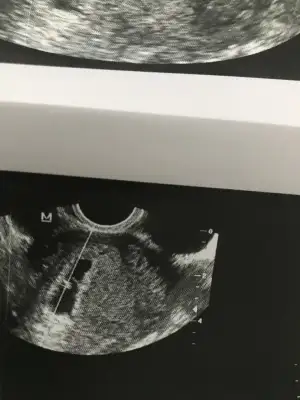

Hayirlisi olsun bakalim ilk cocuk oldugu icin farketmiyor bana. cok sagol ilgilendigin icin canimCanım takvimle kesin kız gibi gözüküyor

Hayirlisi olsun bakalim ilk cocuk oldugu icin farketmiyor bana. cok sagol ilgilendigin icin canimCanım takvimle kesin kız gibi gözüküyor

Erkeğe benzettimbanada tahminde bulunun lütfennnn(((Eki Görüntüle 2229395

Bana cvp yok muu??Kızlar 6+6 tahmini olan var mı